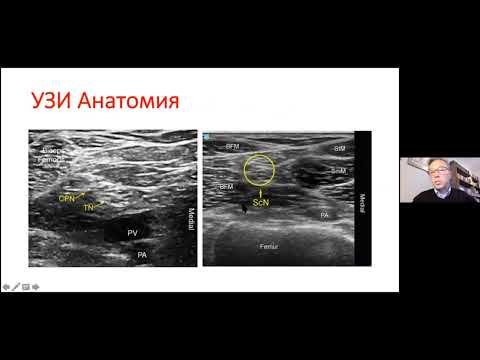

У цьому відео обговорюється блокада сідничного нерва підколінним доступом під контролем ультразвуку, включаючи анатомію, соноанатомію, показання та поради щодо успіху. Відео є перекладеною українською версією оригіналу з Youtube- каналу Regional Anesthesiology and Acute Pain Medicine. Ось посилання на оригінал: • Popliteal Sciatic Nerve Block Опубліковано після отримання дозволу від Global Response Management.